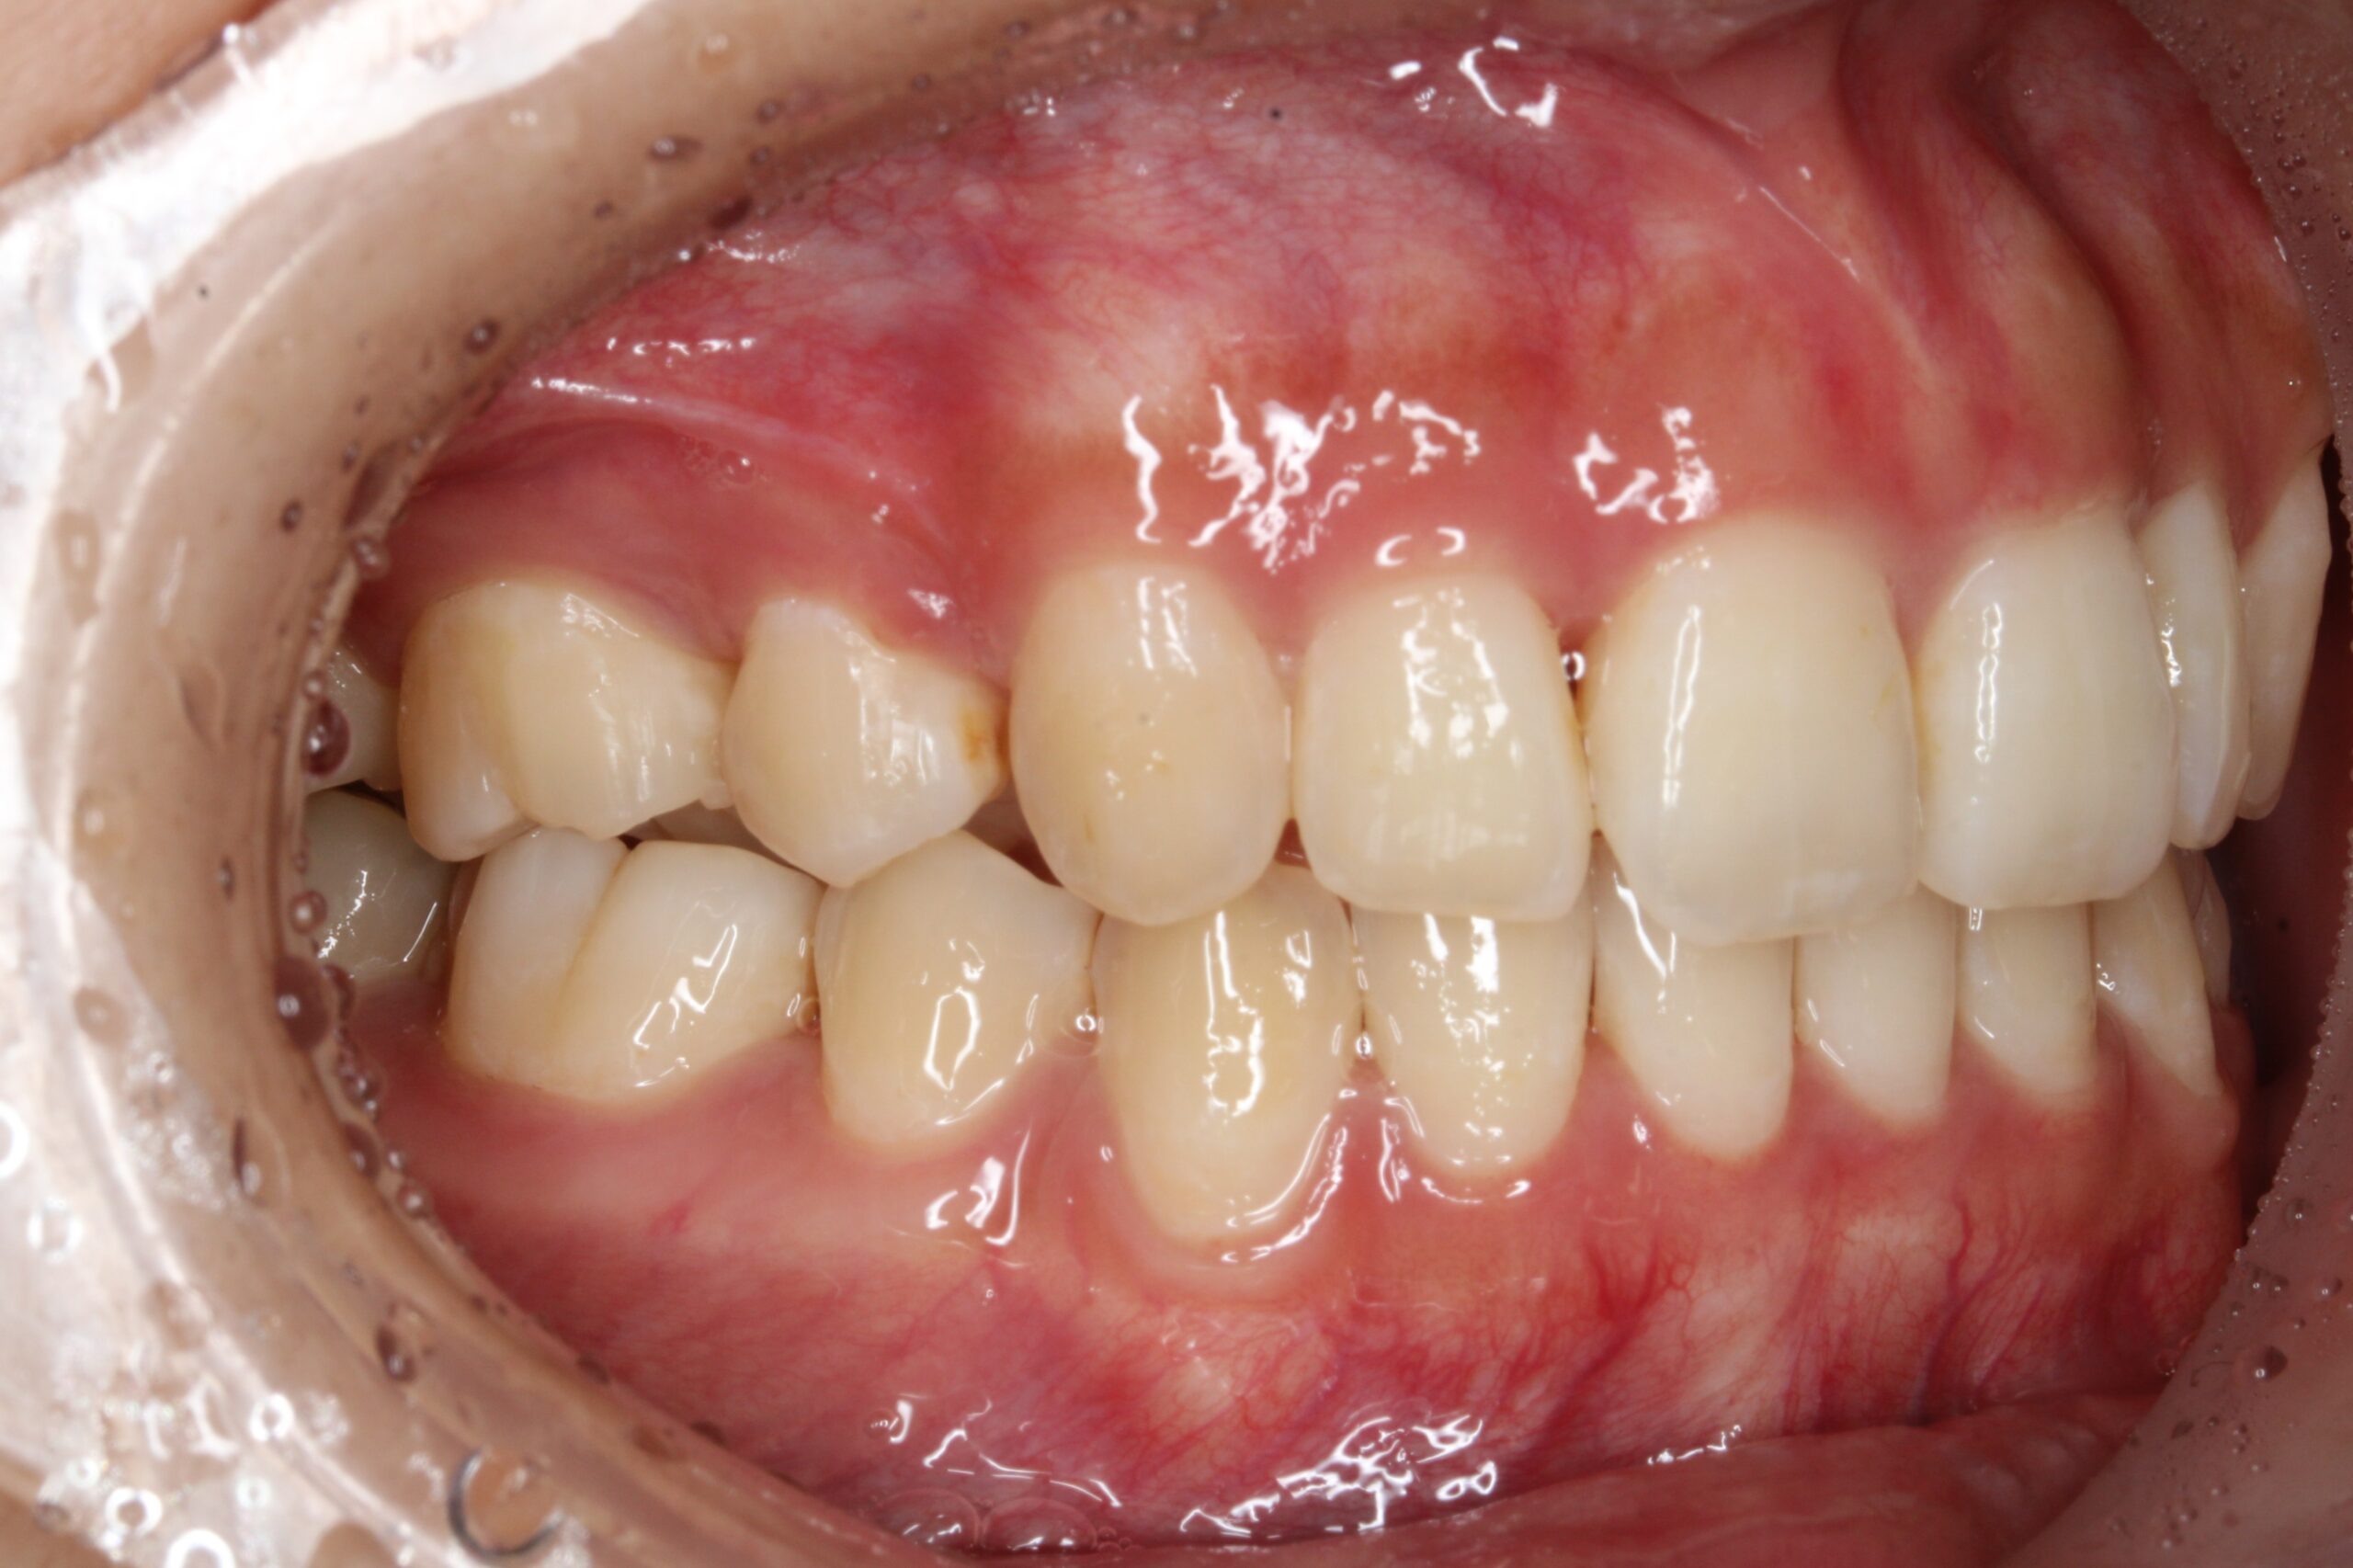

今回ご紹介する患者様は、上下のがたつきを気にされており、矯正検査後叢生Ⅰ級と診断いたしました。

矯正前に、上下小臼歯4本を抜歯いたしました。また、ワイヤー矯正後に、インビザラインで仕上げ矯正を行いました。

矯正術後:右側

| 主訴 | 上下のがたつきが気になる |

| 治療期間 | ・ワイヤー矯正:23カ月 ・インビザライン矯正:15か月 |

| 治療費用 | 1,100,000円(税込) |

| 治療内容 | 患者様は、上下のがたつきを気にされており、矯正検査後叢生Ⅰ級と診断いたしました。矯正前に、上下小臼歯4本を抜歯いたしました。また、ワイヤー矯正後に、インビザラインで仕上げ矯正を行いました。 |